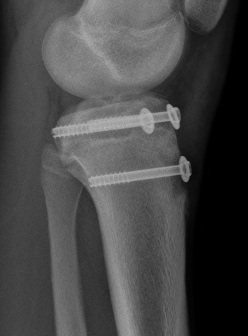

Type I /Type II

Technique

Screw +/- anchor fixation +/- tension band fixation of tibial tubercle and patella tendon

- screw +/- washer in fragment if large

- can supplement with Krackow sutures in patella tendon and fixed distally with suture anchors